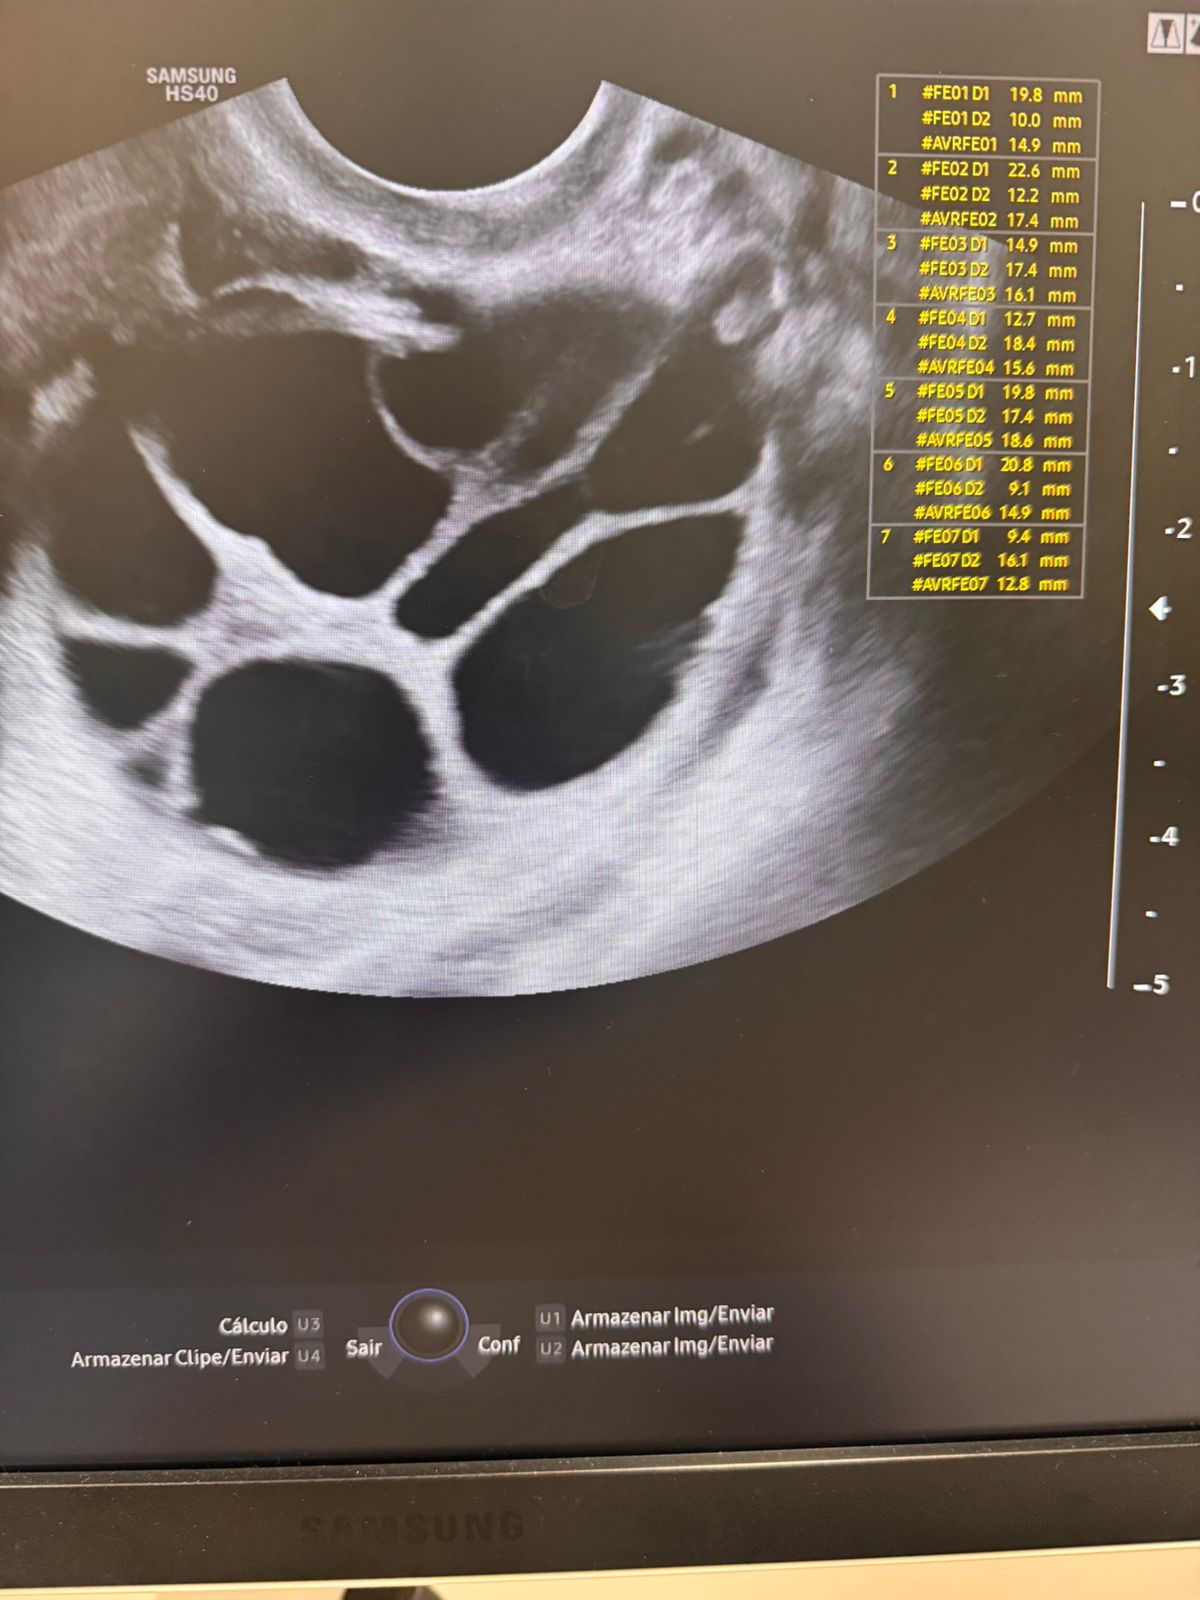

O Congelamento de Óvulos é uma técnica que permite à mulher preservar sua fertilidade, armazenando seus óvulos em seu estado mais saudável para uso futuro. Indicado para quem deseja adiar a maternidade ou precisa realizar tratamentos que podem afetar a fertilidade, o procedimento é minimamente invasivo. Após a coleta, os óvulos são congelados e armazenados em laboratório de forma segura.

Na W.care, oferecemos tecnologia avançada e acompanhamento especializado, garantindo tranquilidade em cada etapa do processo. O congelamento de óvulos oferece à mulher a liberdade de planejar sua maternidade no momento certo, com mais segurança.

Congelamento de óvulos